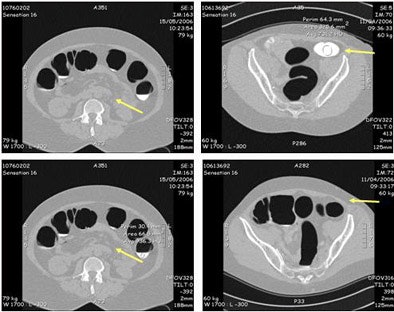

![]() |

| Stool tagging was less successful than fluid tagging, yielding homogeneous tagging results in only two patients. As a result, extra time was needed to distinguish this stool from colonic polyps and mucosa. Images courtesy of Dr. Didier Bielen. |

Residual stool was present in varying amounts in most patients, and stool tagging was homogeneous in just two patients, Bielen said. Even so, the inhomogeneously tagged stool was relatively easy to distinguish from lesions by its texture, and as it changed position between supine and prone scanning.